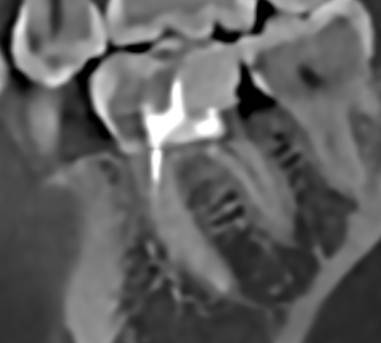

В начале января лечилт зуб в гос поликлинике, от него откололся кусочек ,врач закладывала лекарство для удаления нерва ,через 2 недели пломбировали каналы . Делали все без коффердама. Через 1,5 мес зуб стал беспокоить ,пошла сделала кт ,на кт обнаружиллсь ,что пропустили канал . Плюс сам зуб ,как по мне выглядит странно  ,как будто он очень сильно внутри распилен. Внизу зуба где начинается корень очень тонко. Консультировалась с несколькими врачами. Один сказал ,что не будем лезть в остальные каналы,они нормально пройдены ,найдём один под микроскопом и его только сделать видимо за один визит.  Пошла получить другое мнение  говорят ,что переделывать надо все ,но это все равно без гарантии ,в зубе осталось мало тканей и он треснуть может в любом случае. И все это обойдётся в крупную сумму . Вопрос что делать, можно ли пройти один канал ,чтобы не рисковать сломать зуб ,или инфекция от одного канала уже везде? На данный момент зуб реагирует на холодное и горячее ,неприятно при постукивании,покалывает .

могу прикрепить ссылку кт https://disk.picasso-diagnostic.ru/7e7c16a0-fc83-4b39-a91d-09fc2f0f5c6d/lhDs5VIbI6dIe5ZutFBMd83qtBCXS1Z7eVAnHJCdup_o_N0e2keKzT3kTDblJax1bU2DzP4M1Rvwul3J2An3UWsv.jpg.065ec6a69d86164e39dc9f22752fb54e.jpg